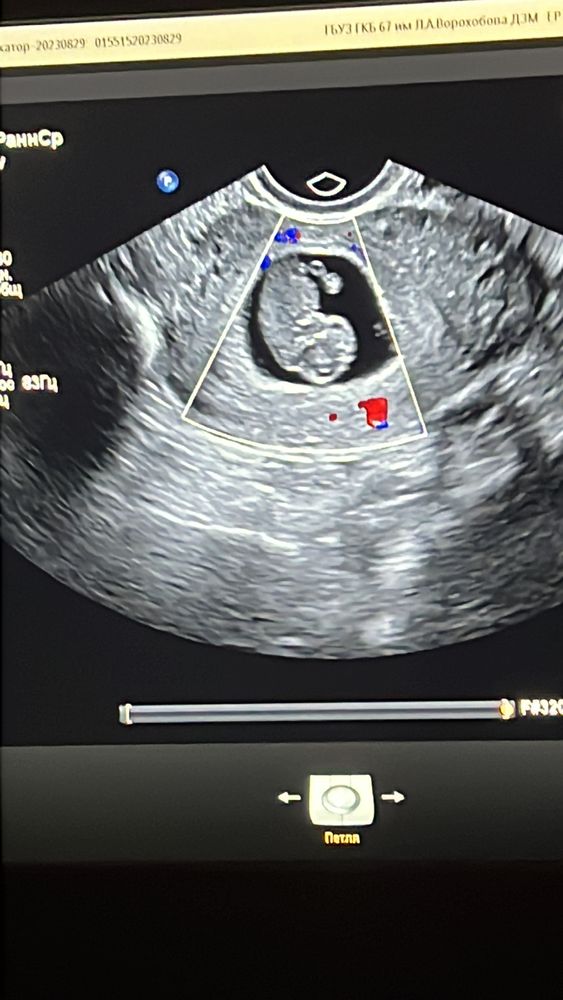

Ирина, я оставила только узи… страх и так останется со мной….

ЗБ на сроке 9 акушкрск. недель Замершая беременность